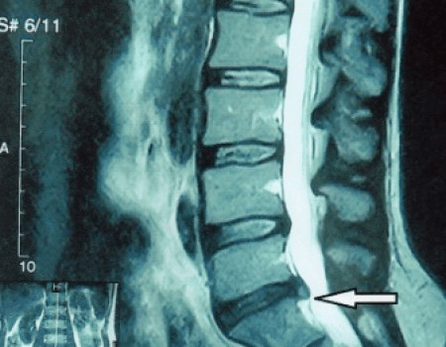

Poiché i dischi intervertebrali stessi sono visibili solo mediante TC o MRI, la risonanza magnetica e la tomografia computerizzata a raggi X sono indicate per chiarire la struttura interna della cartilagine e formazioni come rigonfiamenti ed ernie. Pertanto, con l'aiuto di questi metodi, viene effettuata una diagnosi accurata e il risultato della tomografia costituisce un'indicazione e persino una guida vera e propria per il trattamento chirurgico dell'ernia inguinale nel reparto di neurochirurgia.